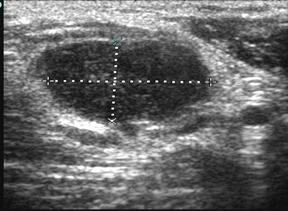

Эхограмма этой же больной через три дня после вскрытия и дренирования гнойника (рис. 6.Б), обращает уменьшение размеров участка гнойного расплавления, отсутствие гнойного затека. Что говорит об эффективности лечения. На следующем рисунке (рис. 7), представлена эхограмма этой же пациентки, выполненная на 11 сутки, с практически восстановленной структурой лимфоузла.

Рис. 7. Эхограмма лимфоузла на 11 сутки после хирургического лечения